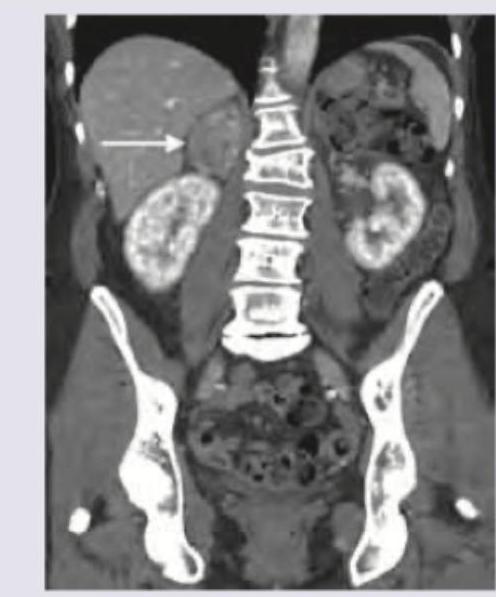

A patient presents with hypertension and hypokalemia. CT abdomen was performed. What is the diagnosis?

Explanation: ***Conn syndrome*** - The image shows a **contrast-enhancing nodule in the right adrenal gland** (indicated by the arrow), consistent with an **aldosteronoma**. - This, combined with **hypertension** and **hypokalemia**, is the classic presentation of **primary hyperaldosteronism** (Conn syndrome). *Pheochromocytoma* - While pheochromocytomas can cause hypertension and are often found in the adrenal gland, they typically present with paroxysmal symptoms such as **palpitations, headaches, and sweating**, which are not mentioned. - They also do not typically cause hypokalemia, as they produce catecholamines, not aldosterone. *Liddle syndrome* - Liddle syndrome is a **genetic disorder** causing **severe hypertension and hypokalemia** due to increased renal sodium reabsorption, mimicking hyperaldosteronism. - However, it is characterized by **low plasma renin activity** and **low aldosterone levels**, and there would be no adrenal mass on imaging. *Secondary hyperaldosteronism* - Secondary hyperaldosteronism is characterized by **high renin levels** (due to conditions like renal artery stenosis or heart failure) leading to increased aldosterone production. - The presence of an **adrenal mass (aldosteronoma)** points to a primary adrenal pathology, rather than a secondary cause driven by systemic factors.